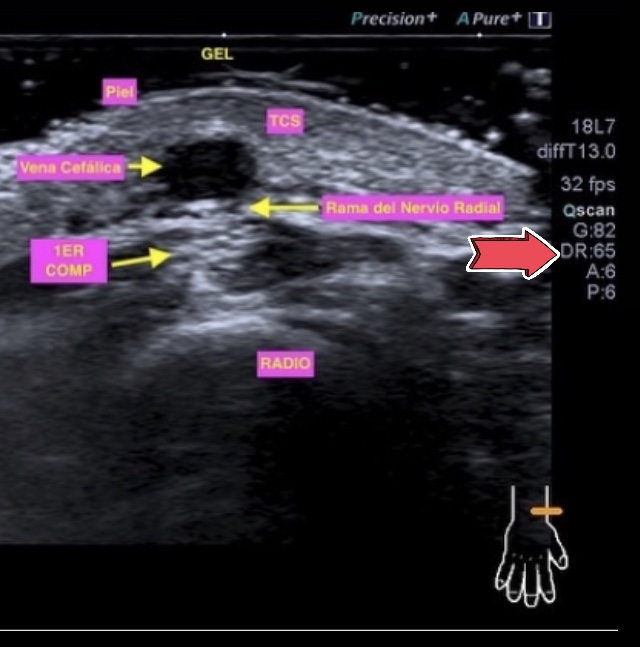

Letra #C #Contraste.

El contraste es la escala de #grises en nuestro ecógrafo.

Depende del #Rango Dinámico como contó María Leal Gondra hace muy poquito en su perfil.

Cuando modificamos este #ajuste estamos manejando la escala de grises debido a que manipulamos e intervenimos sobre la #amplitud de la #onda. Tema que ya hemos explicado en la #A de nuestro #EcoAbecedario.

En la imagen el #RD o #DR que contrasta nuestra imagen.

Tip que no podemos olvidar jamas:

Si aumenta el RD ➡️ – Contraste en la imagen

Si disminuye el RD ➡️ +Contraste en la imagen